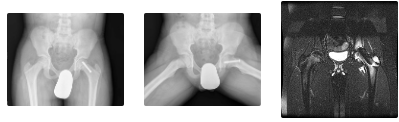

• MRI, may diagnose preslip condition. T1 decreased signal, increased signal on T2

• In one study, nearly 40% of patients with SCFE had bilateral involvement, and of that 40%, half presented initially with a unilateral SCFE but had a subsequent SCFE on the contralateral limb. Radiographs are normal, but the MRI scan shows increased signal about the proximal femoral physis.